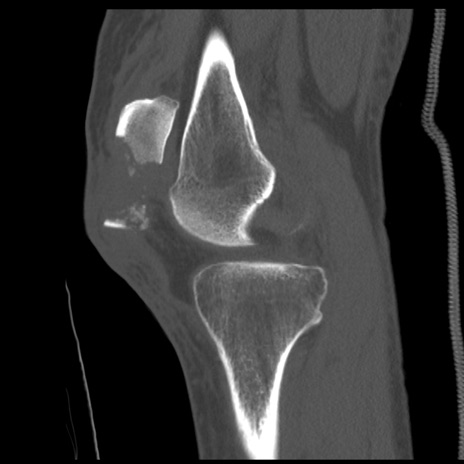

症例28 右膝関節CT(矢状断像)

右膝関節CT